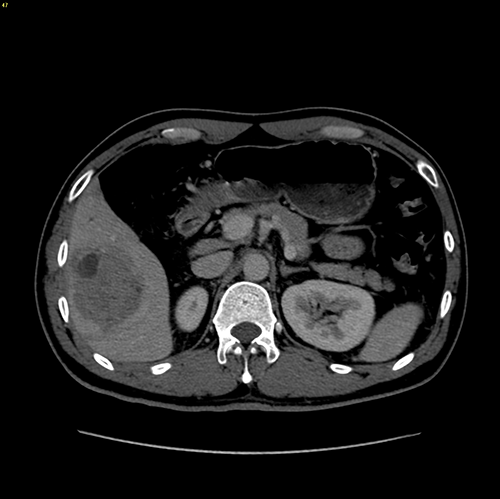

右肝癌-腹腔镜S56肝切除